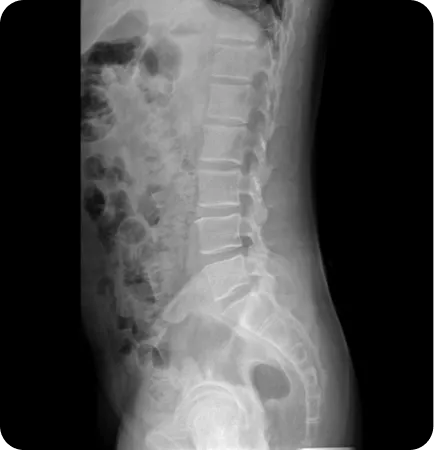

앞으로 기운 골반

(골반 전방경사)

오리 궁둥이 타입으로

골반이 앞으로 기울어져 아랫배가 나오고

허리가 앞으로 휘어서

바로 누워 자기 힘든 유형

• 허벅지 앞쪽과 허리 근육을 이완하고 복근과 엉덩이 근육을 강화하는 도수치료

• 천골 및 장골변위를 교정하는 추나요법

• 평발인 경우 맞춤깔창 처방